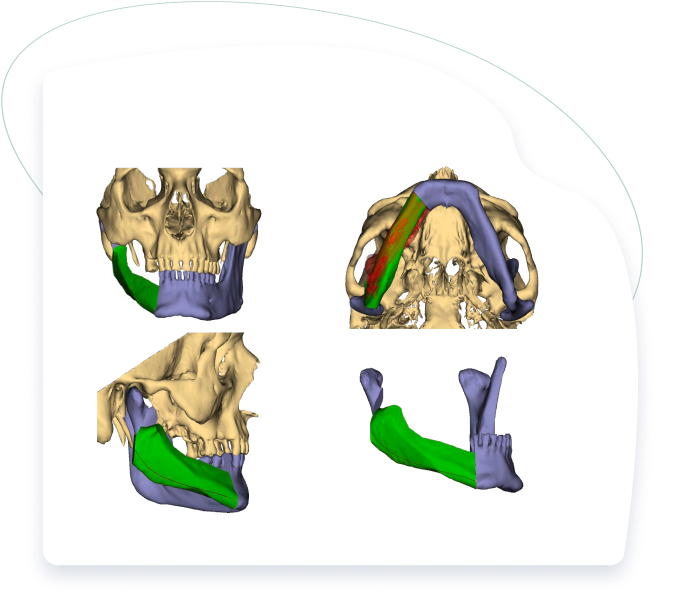

TMJ Disorders

(Temporal Mandibular Joint Disorders)

Expert treatment for jaw joint disorders causing pain, clicking, and limited mouth opening. Our comprehensive approach includes detailed assessment and both surgical and non-surgical treatments, from conservative management and arthroscopy to complex joint reconstruction, preserving natural function.